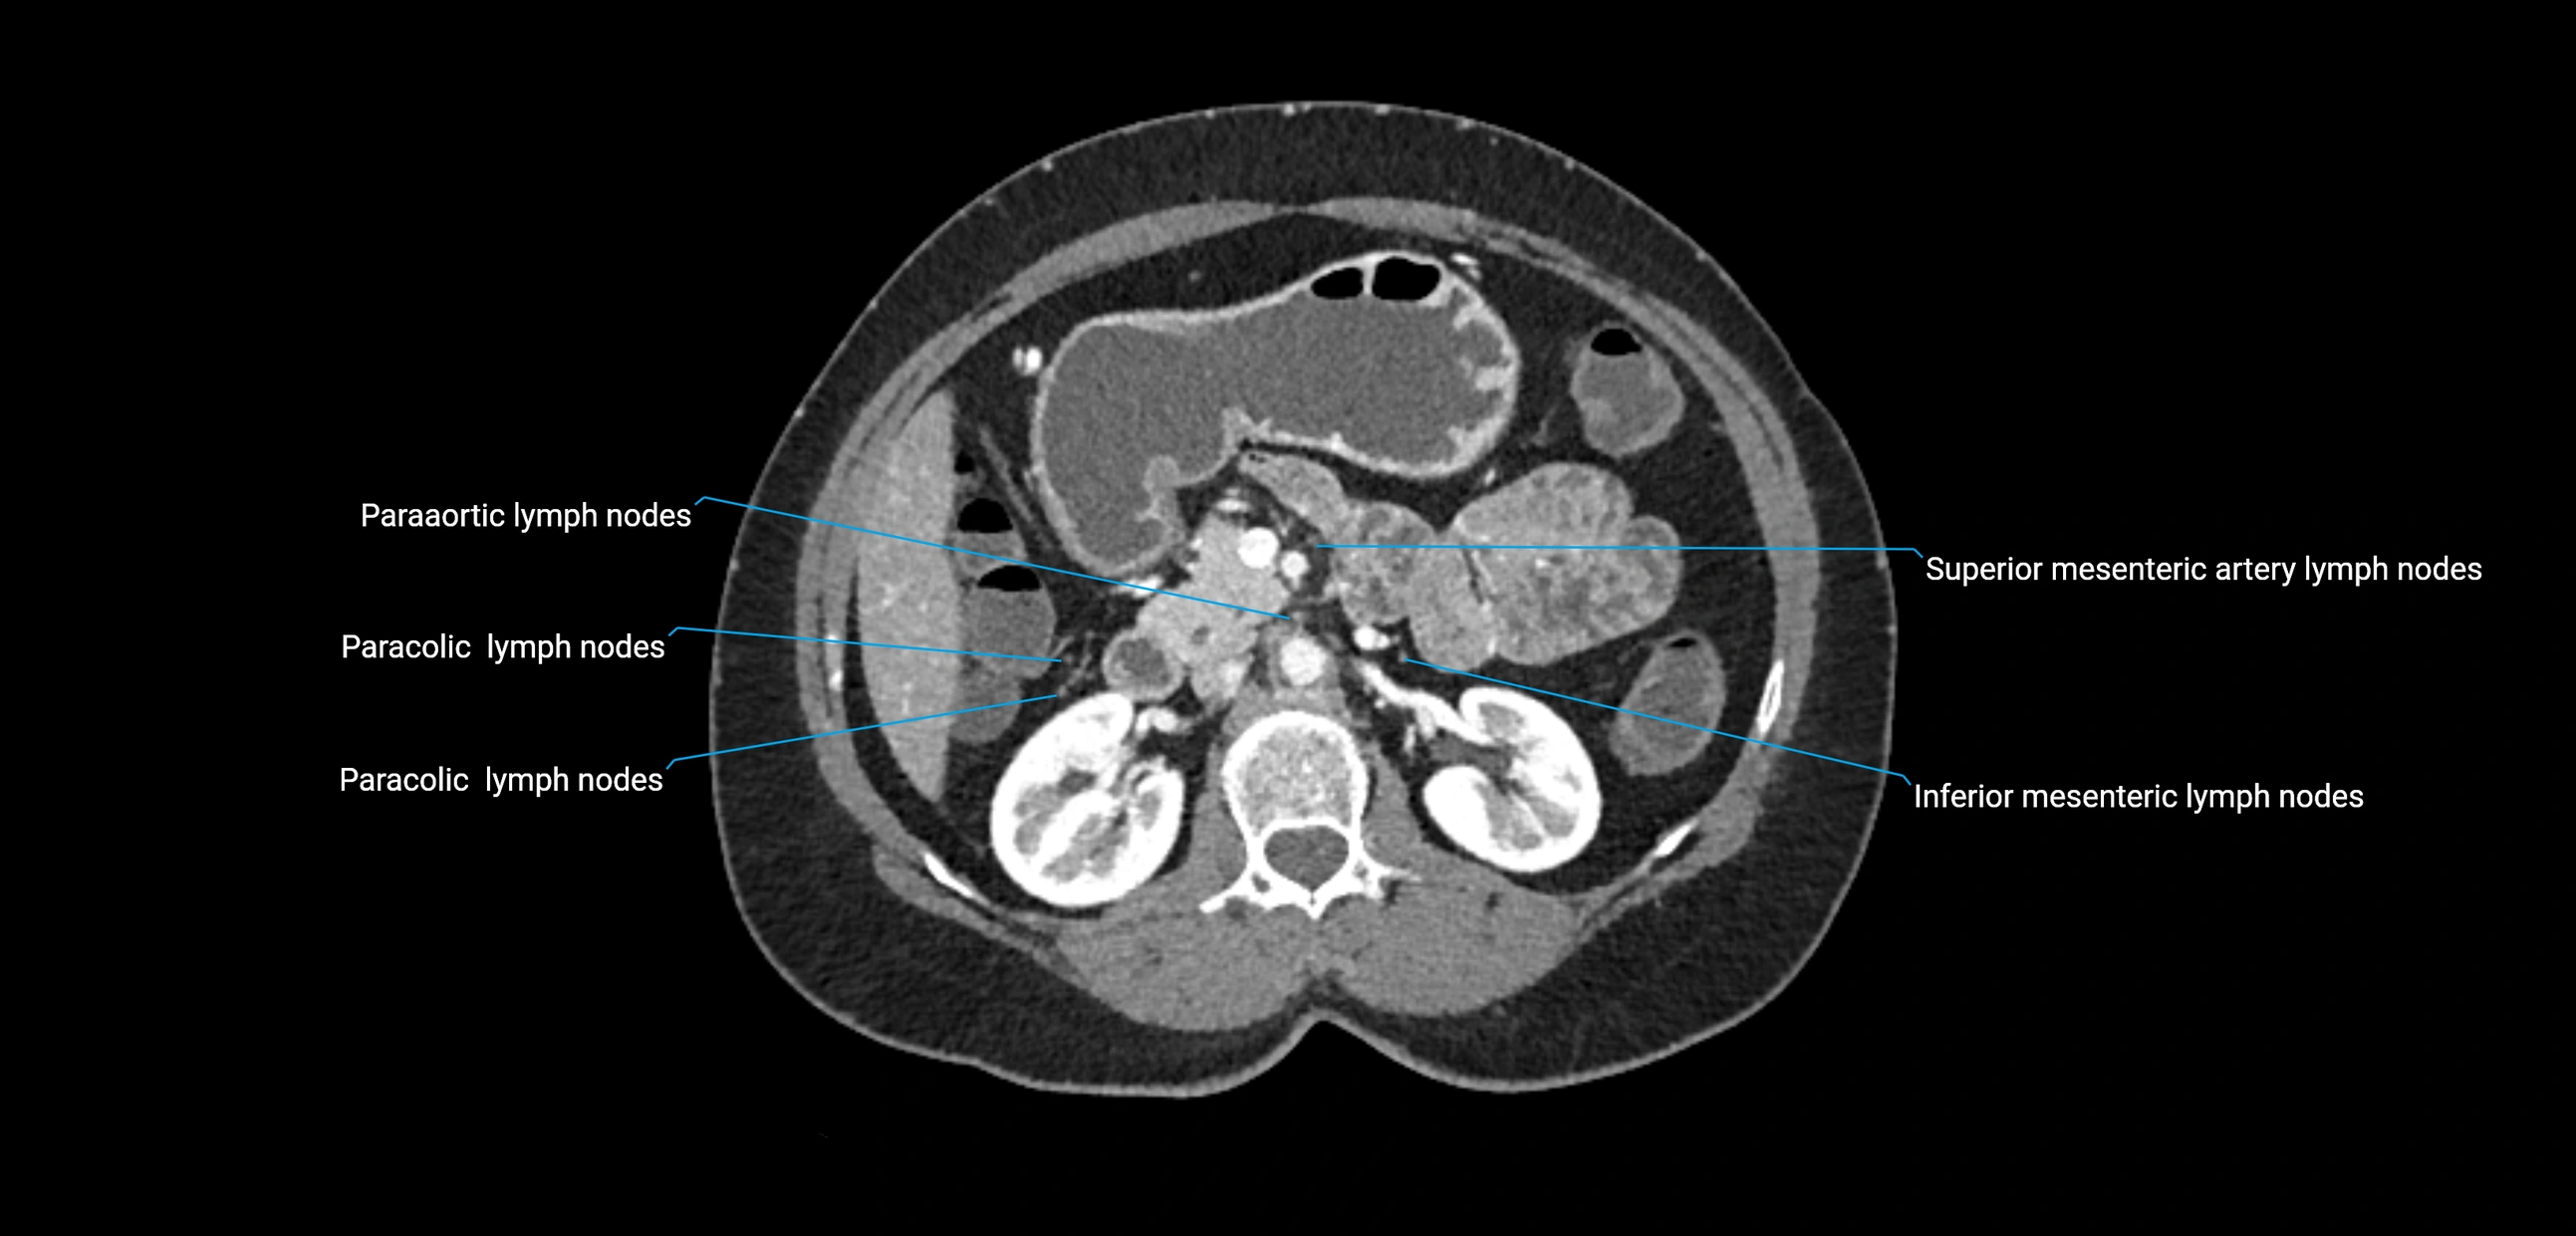

CT Appearance

CT Pre-Contrast:

• Nodes appear as soft-tissue density nodules adjacent to the aorta and IVC

• Calcification may be seen in chronic infections (e.g., tuberculosis)

CT Post-Contrast:

• Normal nodes enhance homogeneously

• Malignant nodes may show heterogeneous enhancement, central necrosis, or conglomerate formation

• Size >1 cm short axis is suspicious, though morphology and distribution are equally important